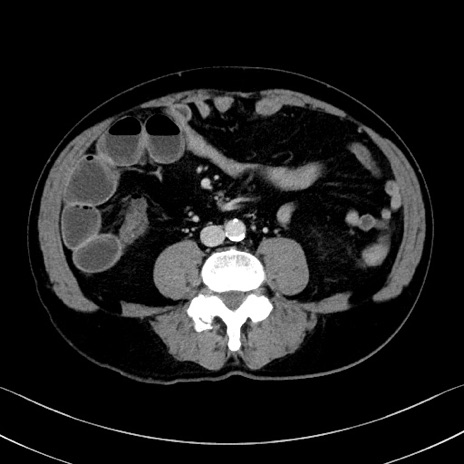

症例35(横断像)

【症例】70歳代 男性

【主訴】腹部膨満、嘔吐

【現病歴】昨日より腹部膨満感出現。本日増悪し、仙痛出現。嘔吐あり、受診。

【既往歴】糖尿病、胆摘後

【身体所見】BP 149/80mmHg、HR 74/min、BT 35.9℃、腹部:膨満、軟、圧痛なし。腸雑音減弱あり。上腹部正中切開瘢痕あり。

【データ】WBC 13500、CRP 1.72